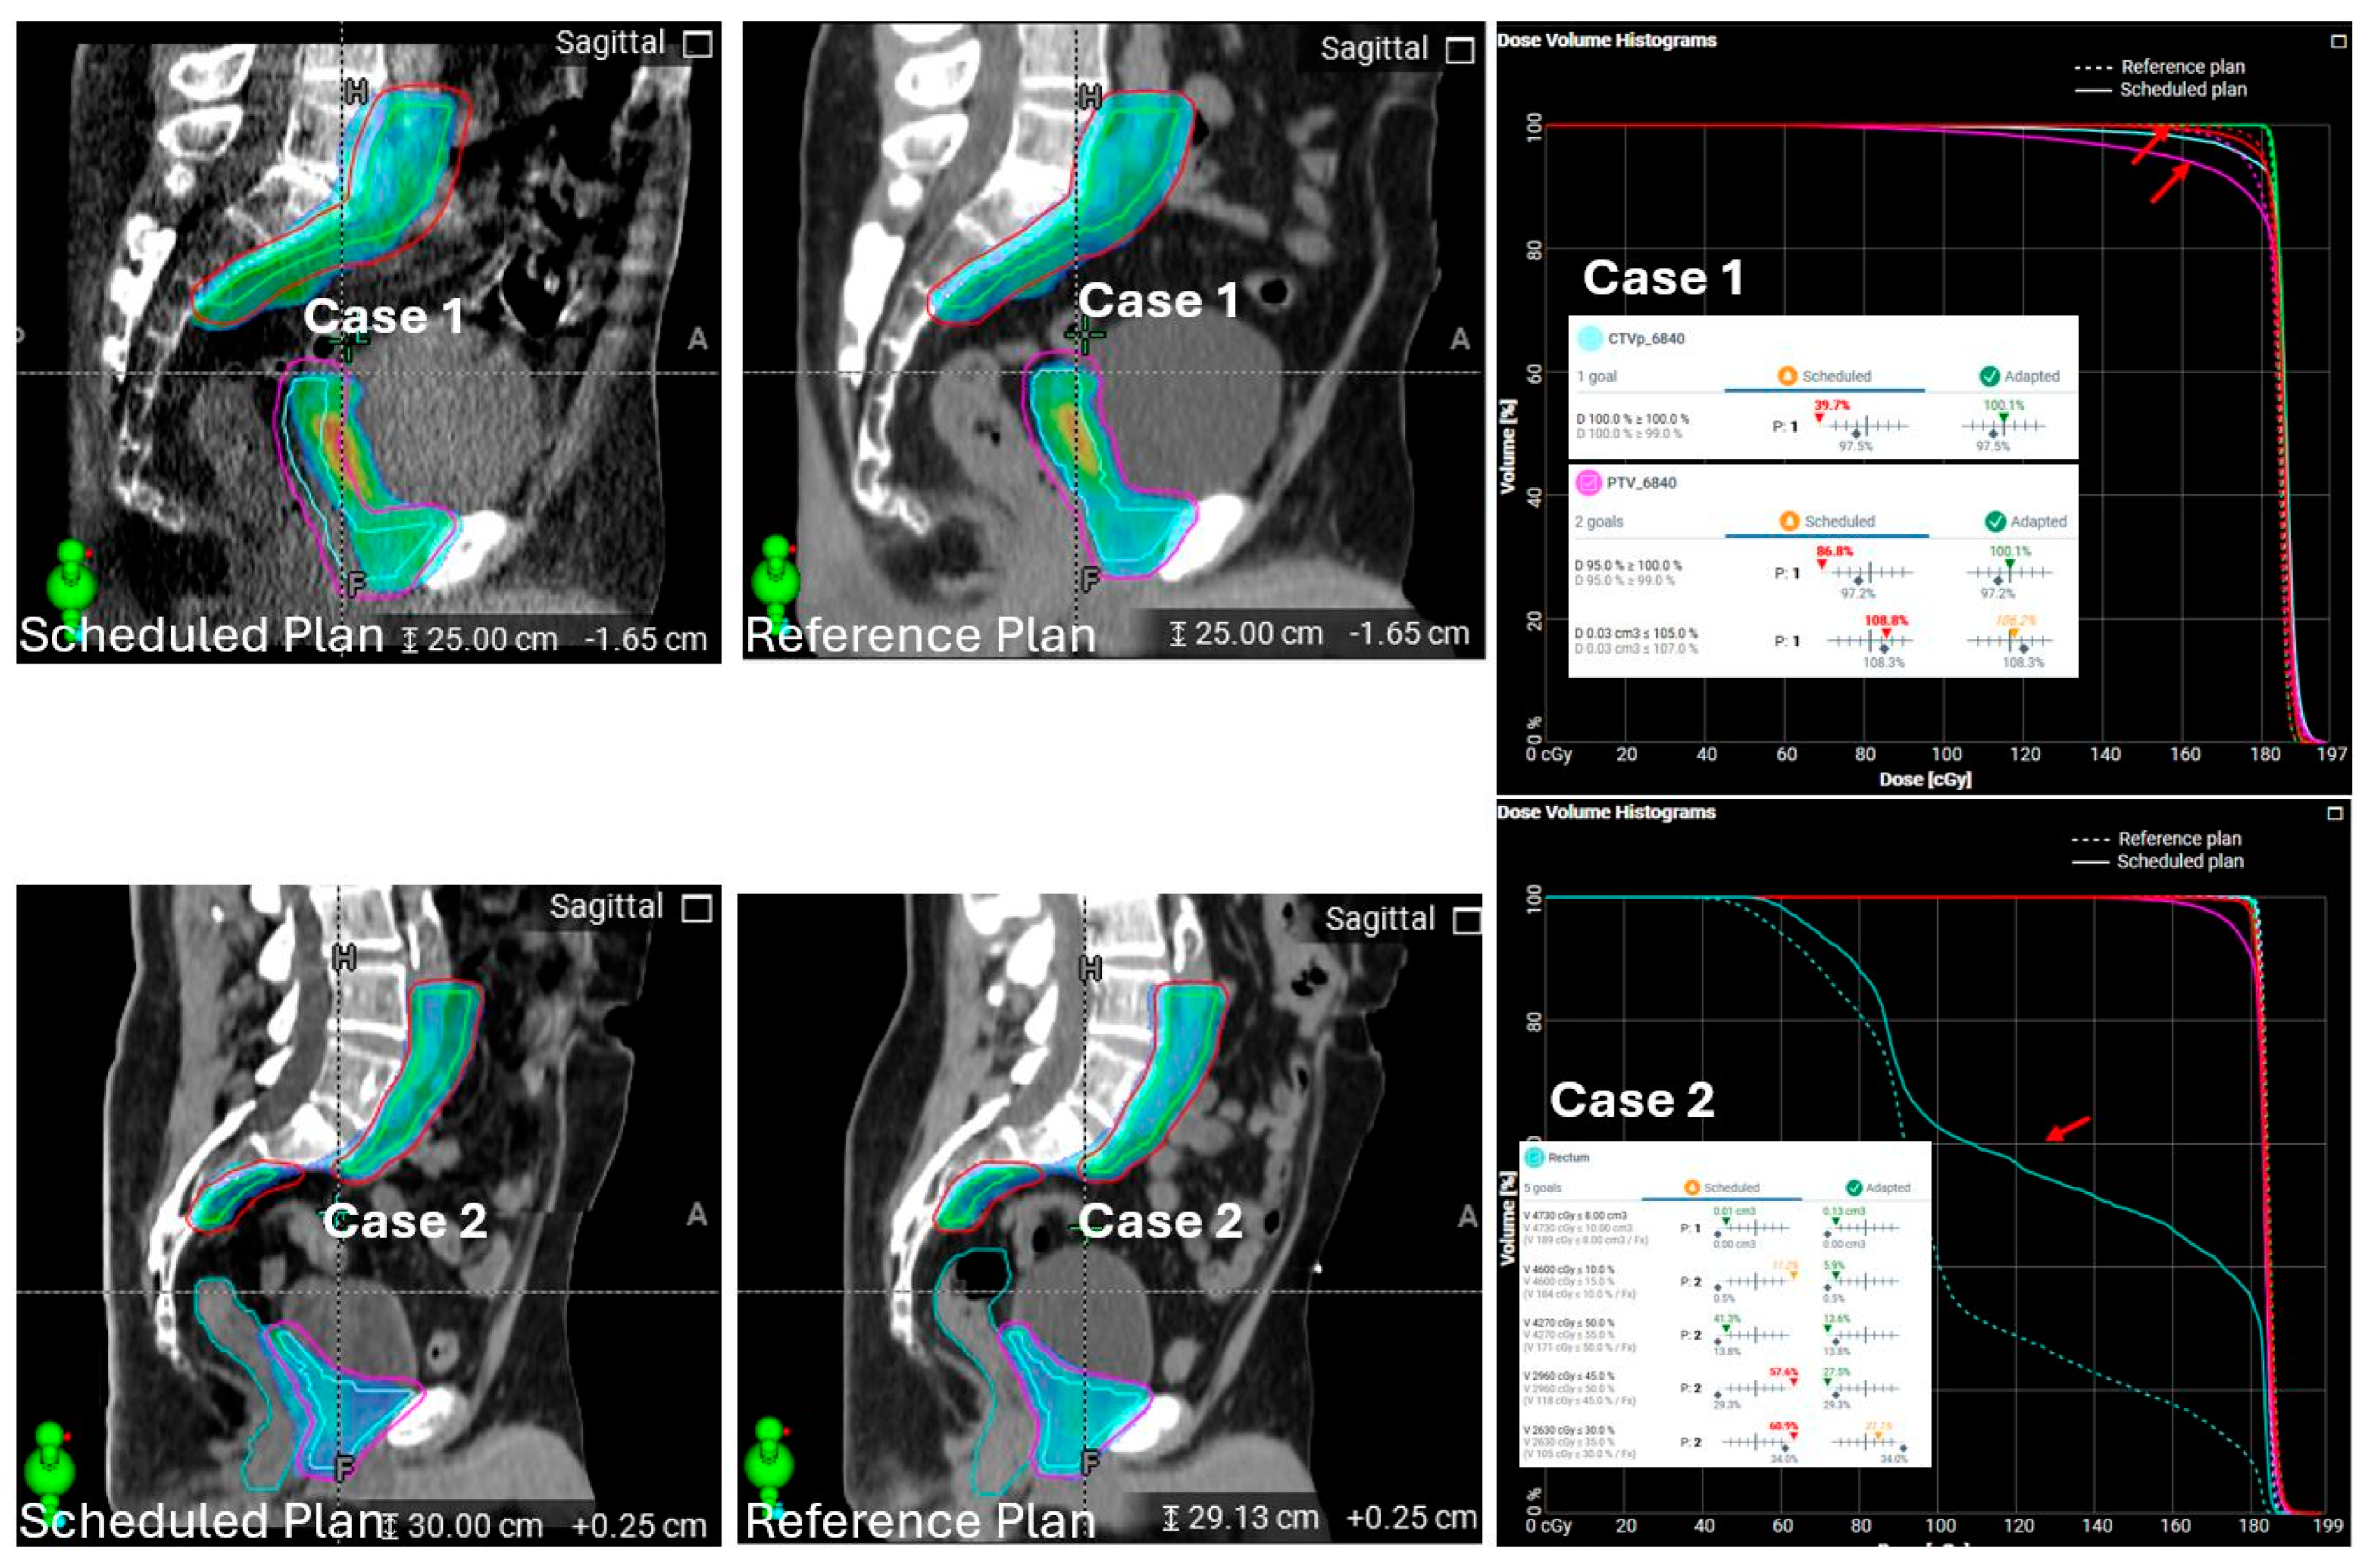

3.2.1. System-Driven Issues

3.2.2. Patient-Driven Challenges

3.2.3. Treatment Planning and Execution Failures